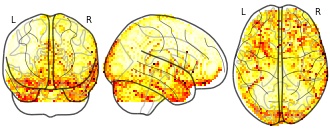

"name": "VBM_HeterogeneityMap",

"description": "Abnormal gray matter in BPD. Brain regions with significant heterogeneity (i.e. between-study variance) in the comparison of patients with BPD and healthy controls. Results are thresholded at at p<.005 & k>20. Note: Results are based on meta-analysis of group comparisons. Note2: Results were updated (see Erratum for this publication)",

"add_date": "2016-01-21T18:23:32.131003+01:00",